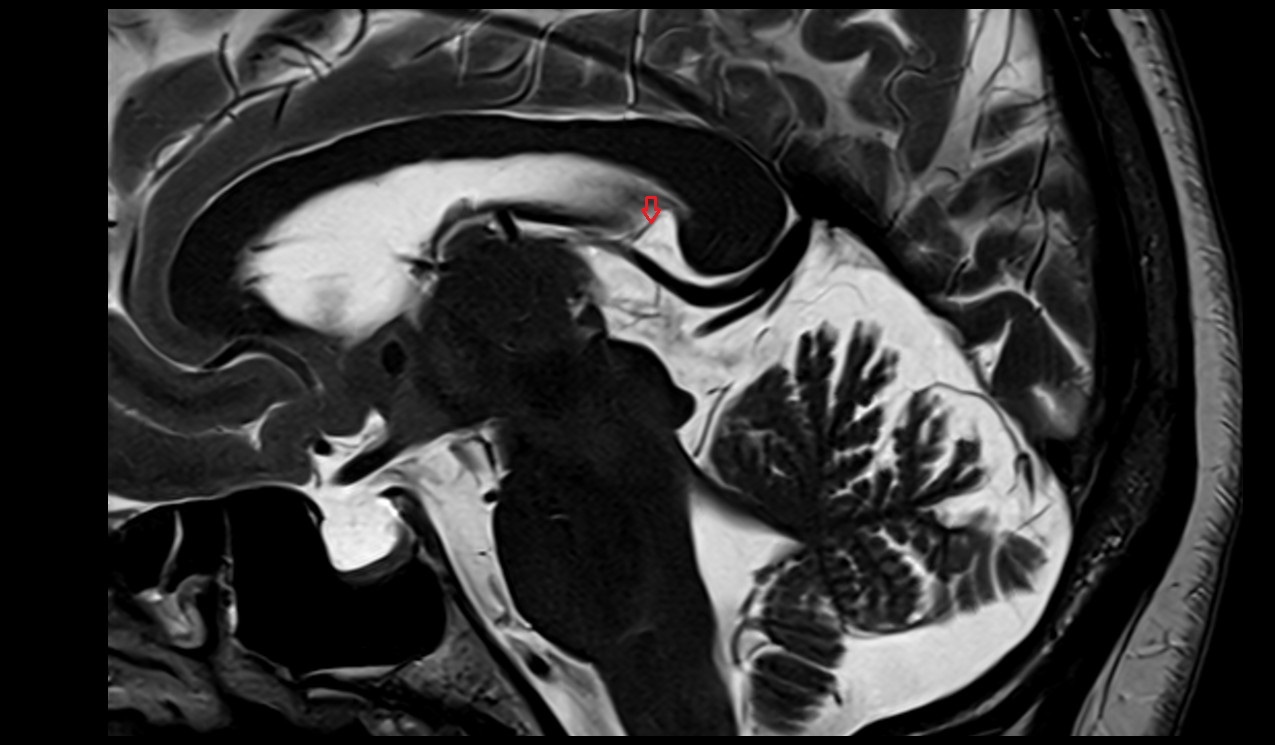

- Fetal brain

- Fetal caudate nucleus

- Fetal thalamus

- Fetal pons

- Fetal cerebellum

- Fetal occipital lobe

- Fetal temporal lobe

- Fetal parietal lobe

- Fetal frontal lobe

- Fetal third ventricle

- Fetal fourth ventricle

- Fetal lateral ventricle